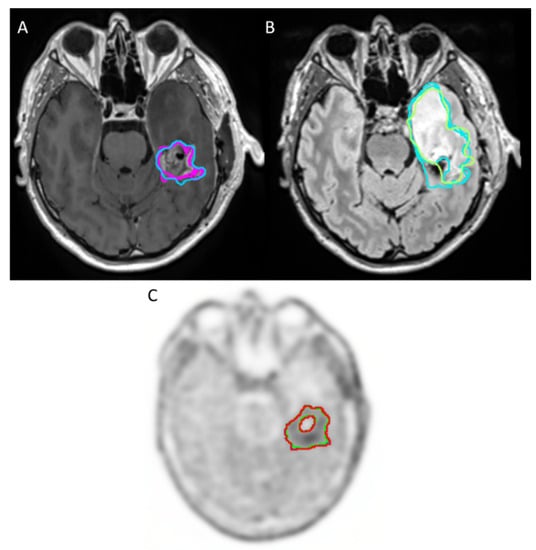

2.3.1. MRI Delineation

2.3.2. 18F-FET PET/CT Delineation